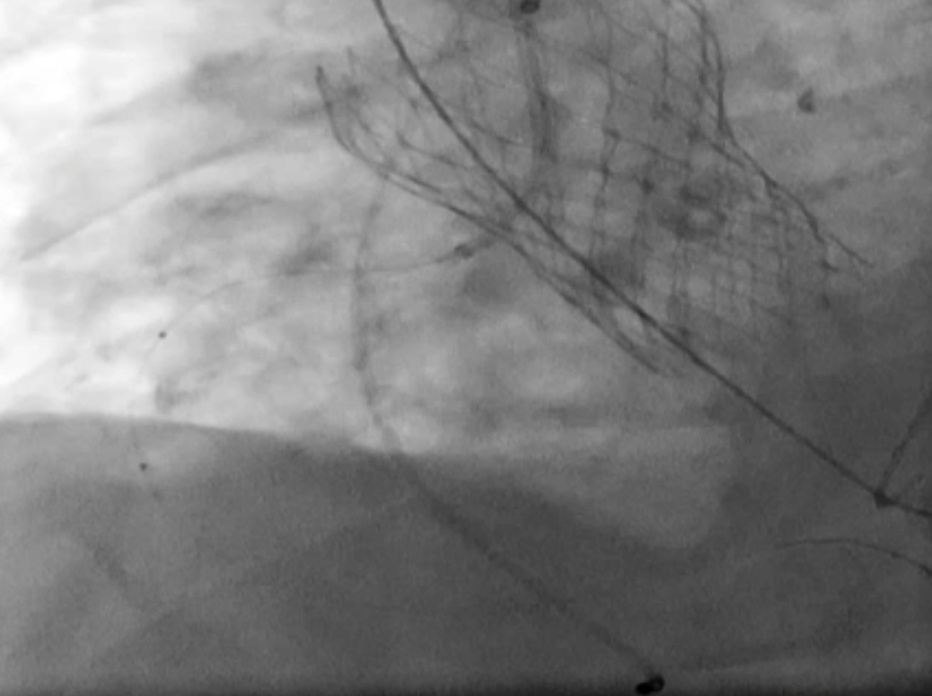

CT confirmed absence of commissural misalignment of failed CoreValve, and commissural alignment of the Evolut PRO was achieved by orienting the delivery system with the flush port at 3 o¡¯clock. The inflow portion of the the Evolut PRO was implanted at the same level as the failed CoreValve. Aortography post-implantation confirmed no RCA obstruction.

To mitigate the risk of coronary obstruction, the RCA was protected using a coronary guidewire and balloon. CT confirmed absence of commissural misalignment of failed CoreValve, and commissural alignment of the Evolut PRO was achieved by orienting the delivery system with the flush port at 3 o¡¯clock. The inflow portion of the the Evolut PRO was implanted at the same level as the failed CoreValve. Aortography post-implantation confirmed no RCA obstruction, allowing safe removal of the guidewire and balloon. The procedure was uneventful, with no conduction disturbances or paravalvular leak. The functional mitral regurgitation resolved immediately after the procedure.